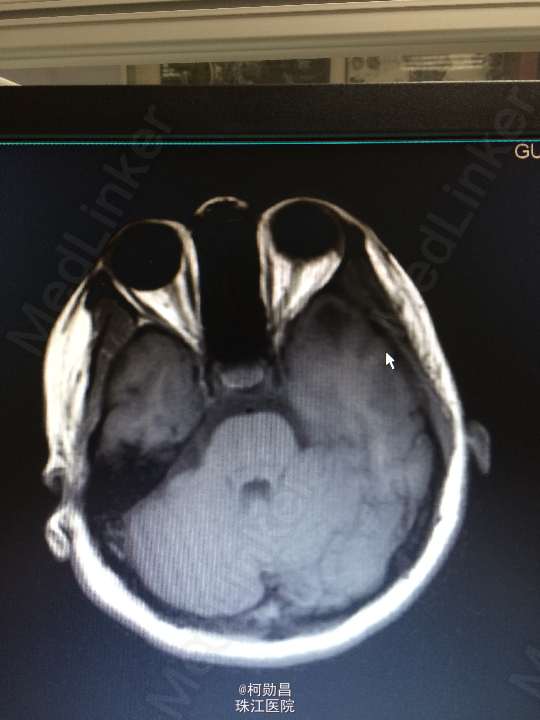

间断性眩晕伴头痛10余年 患者10年来无明显诱因间断性出现起床后眩晕,为天旋地转状,伴头痛、恶心、呕吐,严重时会出现肢体抽搐,双眼紧闭,无口角抽搐、意识障碍等。大约每年发作一次,数小时后自行好转,自服药物治疗(具体不详)。患者1个月前再次出现上述症状,遂至我院诊治:查头颅MR提示:左侧颞极前部皮层及皮层下异常信号影,不排除肿瘤。建议增强扫面。

查体:神经系统查体未见明显异常 头颅CT:左颞极前部占位,建议增强检察 头颅MR:左侧颞极前部皮层及皮层下异常信号影,不排除肿瘤。

诊断:脑膜血管瘤 处理:开颅手术切除,术后病理提示:(左颞极)脑膜血管瘤